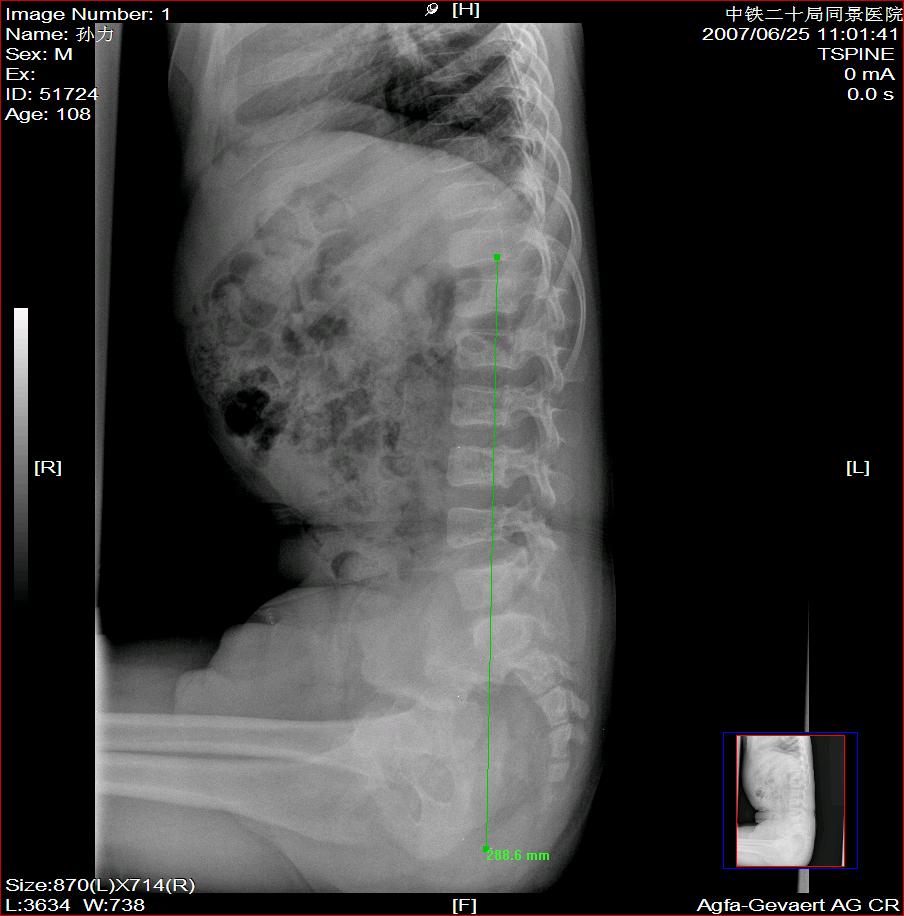

标题: X2504:M17Y,高中生,身高不足1.2米,智力正常 [打印本页]

标题: X2504:M17Y,高中生,身高不足1.2米,智力正常

年龄17岁,身材矮小(1.2m),全身骨骼发育迟缓,骨骺线仍较宽,但全身骨骼骨质正常,智力正常。

骨结构正常,骨骺线与17岁不符,豆状骨未见,相当7-8岁骨龄,结合智力正常,垂体性侏儒可能大。

考虑垂体侏儒的可能。依据1骨龄延迟,骨胳结构正常,智力正常。与甲状腺功能不足区别呆小症病人长骨及骨垢有改变,骨垢较正常小。椎体变扁。考虑垂体侏儒症。

各部比例在正常范围,为均称型侏儒,可见于1、垂体性侏儒。2、致密性骨发育不全。3、turner氏综合症。本例骨密度正常,皮质边界清,显然不支持致密性骨发育不全,未见掌骨征阳性和指骨优势,turner氏综合症,可基本除外,剩下的只有垂体性侏儒了,建议垂体mri进一步检查,确定诊断。以上主要参考曹来宾教授发表的论文,侏儒症的临床x线分析

全身骨骼发育迟缓,骨骺线仍较宽与年龄不符。考虑垂体性侏儒可能大。